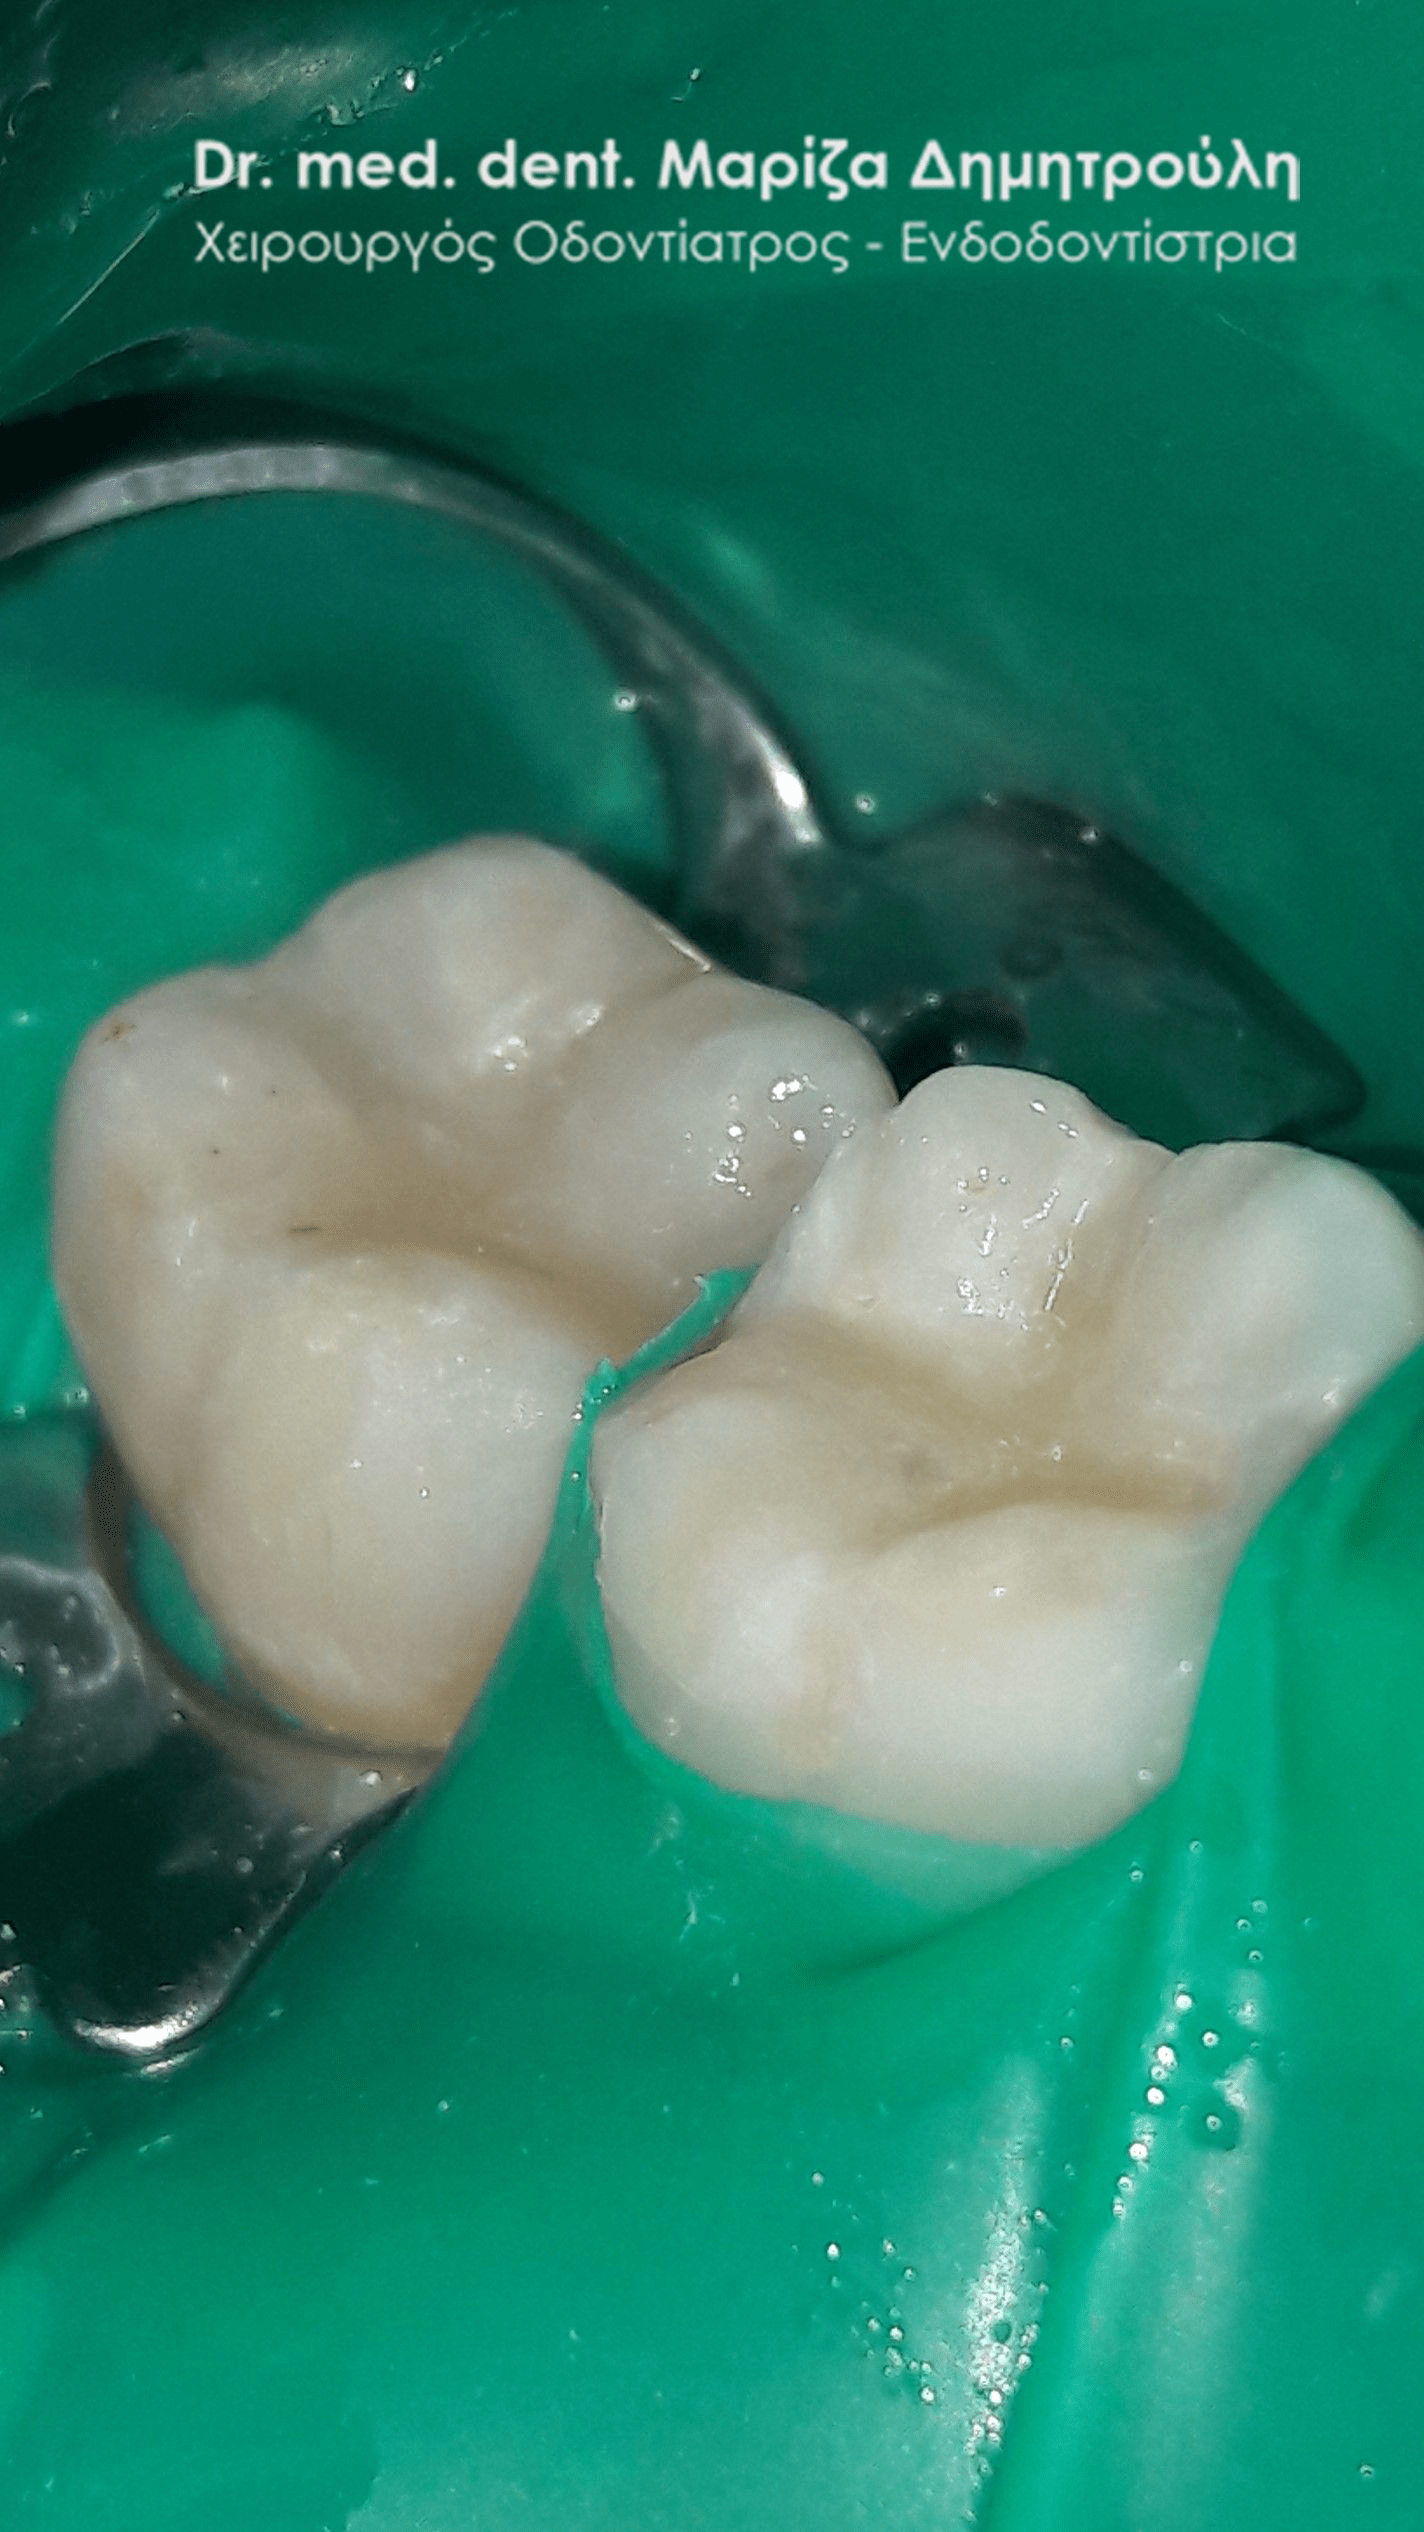

Περιστατικό – Λευκά σφραγίσματα δύο δοντιών

Στο παρόν περιστατικό απουσιάζει η αρχική εικόνα των δύο δοντιών πριν αρχίσει ο εκτροχισμός τους. Διαθέσιμες είναι μόνο η ενδιάμεση εικόνα που παρουσιάζει το εύρος του οδοντικού ελλείμματος στα δύο γομφίους της αριστερής πλευράς της άνω γνάθου και η τελική εικόνα αποκατάστασης των δύο δοντιών.

Η ασθενής αισθανόταν τις τελευταίες μέρες έναν ήπιο πόνο κατά τη μάσηση τροφών. Μετά την κλινική εξέταση του στόματος διαπιστώθηκε η ύπαρξη τερηδονικών κοιλοτήτων στους δύο άνω αριστερούς γομφίους. Αποφασίστηκε με τη συναίνεση της ασθενούς η αντικατάσταση των σφραγισμάτων. Στον πρώτο γομφίο διορθώθηκε μόνο η μισή έκταση του παλιού σφραγίσματος, καθώς κρίθηκε οτι δεν ήταν απαραίτητη η αφαίρεση ολόκληρου του παλιού σφραγίσματος.

ΠΡΙΝ

META